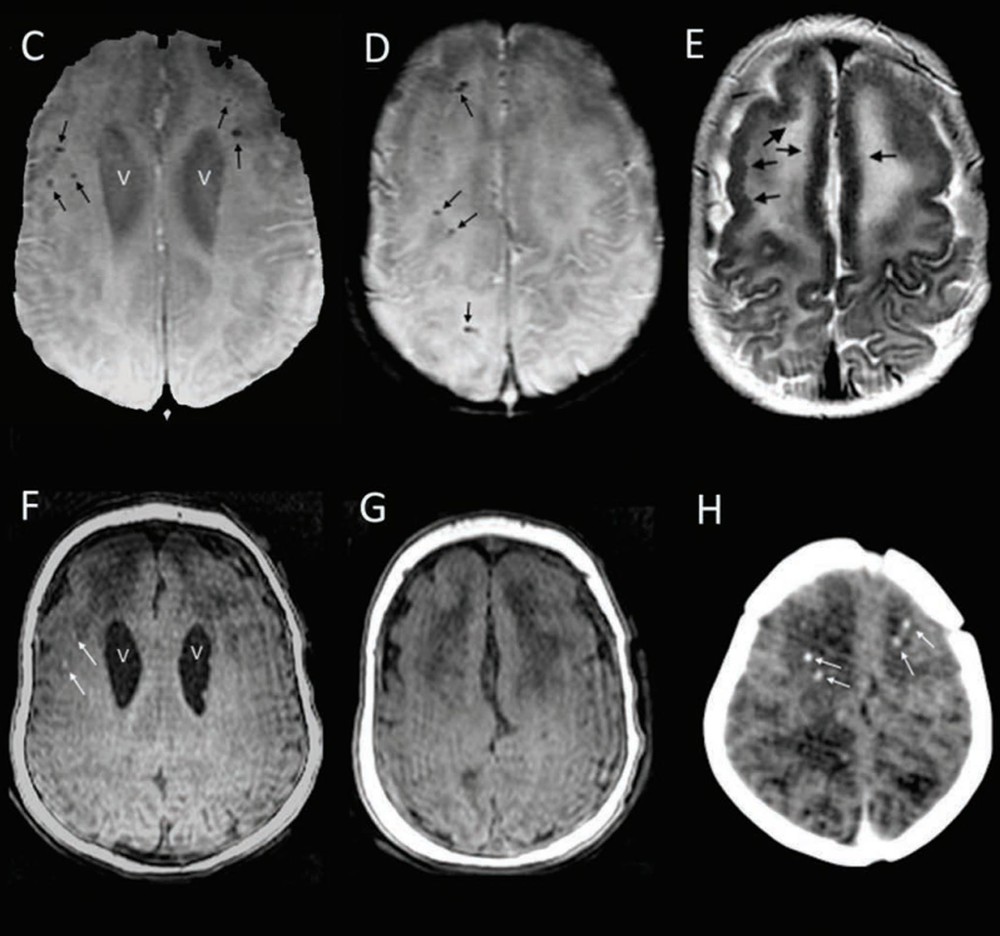

Alguns bebês infectados pelo vírus da zika nascem aparentemente saudáveis, mas têm malformações cerebrais e depois desenvolvem a microcefalia, um crescimento da cabeça abaixo da média, segundo um estudo divulgado na terça-feira (22).

Os pesquisadores já sabiam que o zika podia causar problemas no desenvolvimento cerebral mesmo quando não havia sinais externos de microcefalia. Mas o novo trabalho é o primeiro a mostrar o desenvolvimento dos sintomas após o nascimento.

"Uma microcefalia pode não ser evidente no nascimento, mas se desenvolver mais tarde com anormalidades cerebrais subjacentes", disse o estudo.